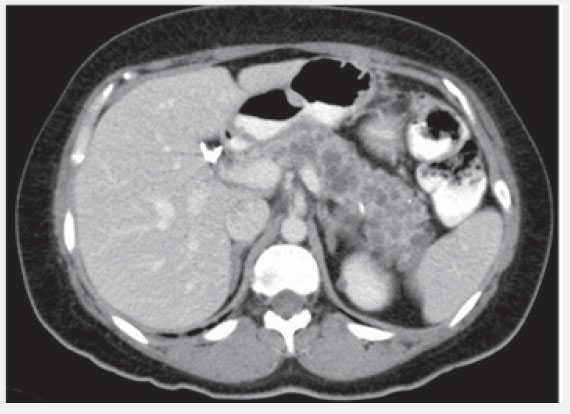

Figura 2. Quistes pancreáticos y renales.